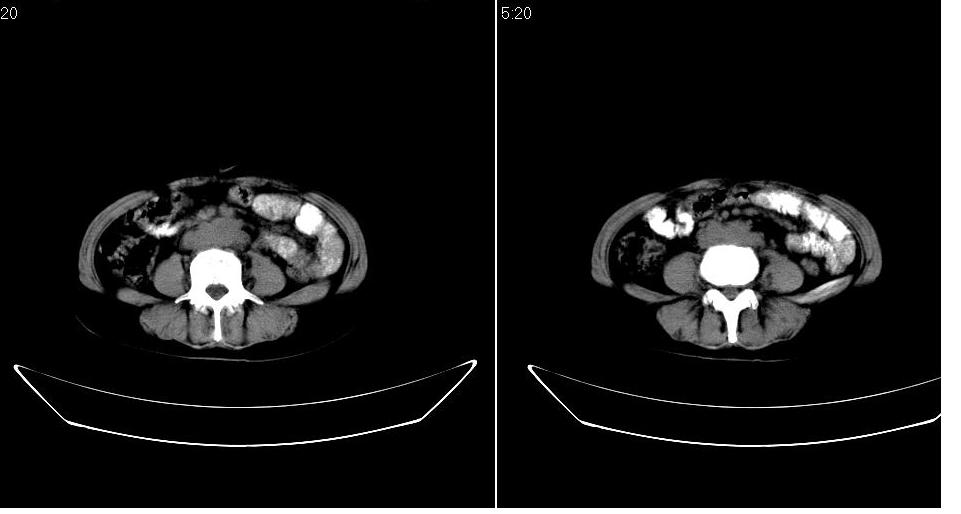

女 53岁,大便每天四到五次,变细,伴有粘液,病人家属说,去年五月在外院行子宫肌瘤术。

腹膜后多发肿大淋巴结肿大并融合改变;右侧回盲部可见团块样软组织影,不规则;

腹膜后诸多淋巴结,右侧髂窝软组织块影,综合患者大便次数、形状改变,考虑结肠回盲部肿瘤

盆腔内的肿块与升结肠没有什么关系,我考虑1来于小肠 2就是个融合的盆腔淋巴结 不能解释的是病人为什么大便变细,黏液便,会不会是直肠有浸润,我看直肠壁好象有点厚

回盲部可见团块样软组织影,不规则;腹膜后多发肿大淋巴结肿大并融合改变;考虑回盲部肿瘤并腹膜后淋巴结转移,建议钡剂灌肠或增强检查.

双侧盆腔均可见不规则形软组织肿块影,似为结节状影融合而成,但以右侧为甚,腹主动脉与下腔静脉周围亦可见多个肿大淋巴结.

结合临床手术史考虑:盆腔与腹膜后多发性淋巴结转移(原发灶可能是原来的\"子宫肌瘤\"恶变或并非\"子宫肌瘤\";回盲部肿瘤不排除)